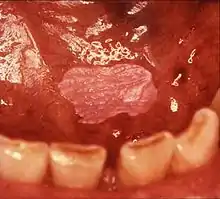

| |

| Leukoplakia on the inside of the cheek | |

Oral leukoplakia is a potentially malignant disorder affecting the oral mucosa. It is defined as "essentially an oral mucosal white lesion that cannot be considered as any other definable lesion." Oral leukoplakia is a white patch or plaque that develops in the oral cavity and is strongly associated with smoking.[8] Leukoplakia is a firmly attached white patch on a mucous membrane which is associated with increased risk of cancer.[4][5] The edges of the lesion are typically abrupt and the lesion changes with time.[4][6] Advanced forms may develop red patches.[6] There are generally no other symptoms.[9] It usually occurs within the mouth, although sometimes mucosa in other parts of the gastrointestinal tract, urinary tract, or genitals may be affected.[10][11][12]

Homogeneous leukoplakia (also termed "thick leukoplakia")[2] is usually well defined white patch of uniform, flat appearance and texture, although there may be superficial irregularities.[2][9] Homogeneous leukoplakia is usually slightly elevated compared to surrounding mucosa, and often has a fissured, wrinkled or corrugated surface texture,[2] with the texture generally consistent throughout the whole lesion. This term has no implications on the size of the lesion, which may be localized or extensive.[2] When homogeneous leukoplakia is palpated, it may feel leathery, dry, or like cracked mud.[2]

Most cases of leukoplakia cause no symptoms,[9] but infrequently there may be discomfort or pain.[2] The exact appearance of the lesion is variable. Leukoplakia may be white, whitish yellow or grey.[29] The size can range from a small area to much larger lesions.[29] The most common sites affected are the buccal mucosa, the labial mucosa and the alveolar mucosa,[30] although any mucosal surface in the mouth may be involved.[2] The clinical appearance, including the surface texture and color, may be homogeneous or non-homogeneous (see: classification). Some signs are generally associated with a higher risk of cancerous changes (see: prognosis).